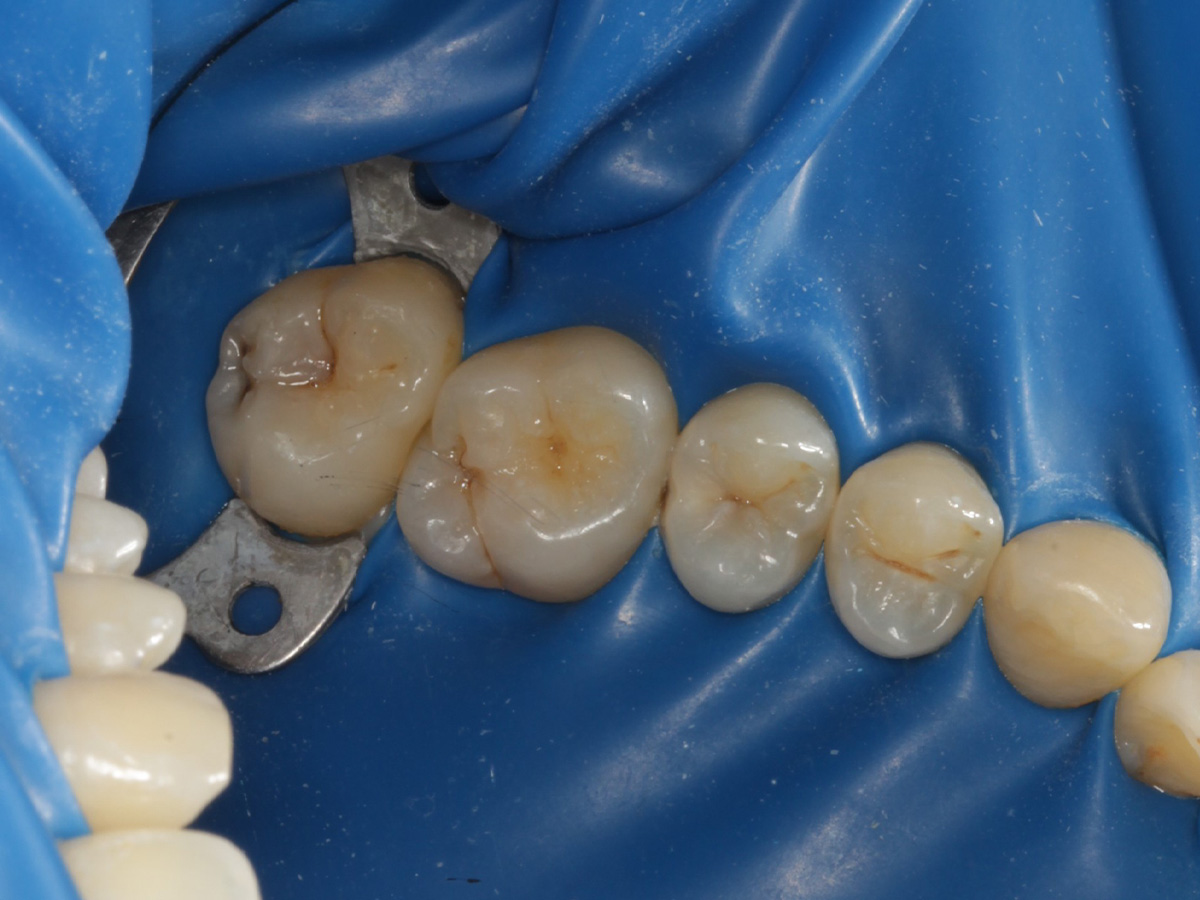

Abbildung 15

Matrize, Twinring, und Keil entfernt; weitere Lichthärtung von bukkal und oral

Abbildung 16

Überschussentfernung/ „Anpolieren“ u.a. trocken mit Sandpapierscheibe

Abbildung 18

Fertige Restauration